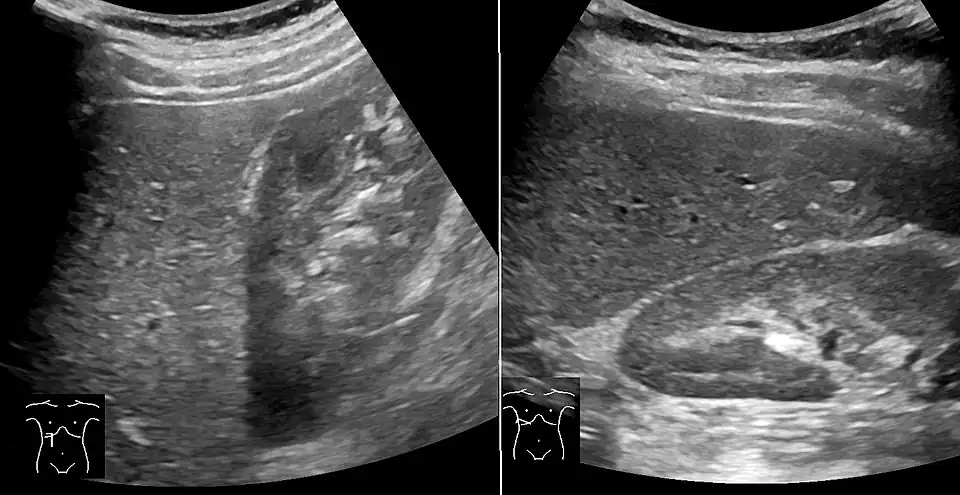

Abdominal ultrasonography with the liver and kidney side by side (left image) may give a false impression of hyperechogenic liver, so it's preferably done with the organ borders facing the ultrasound probe (right image, of the same case). -

Abdominal ultrasonography of focal steatosis. It is distinguished from a tumor by not compressing the hepatic vein.